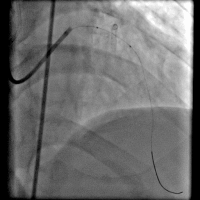

造影结果: 左前降支近段闭塞,回旋支中远段90%狭窄。

手术过程(一): 将Fielder XT 导丝送入回旋支远端真腔,沿回旋支导丝送入Trek 2.5×20 mm球囊到回旋支中段8 atm×10 s预扩,沿导丝Firebird 2.5×29 mm药物支架一枚到回旋支中远段8 atm×12 s释放。

手术过程(三): 微导管支持下ASAHI Gaia 1st 导丝通过前降支真腔。

手术过程(五): 沿导丝送入Firebird 2.5×33 mm药物支架一枚至前降支中段10 atm×12 s释放,沿导丝送入Firebird 3.0×23 mm药物支架一枚至前降支近段14 atm×12s释放。